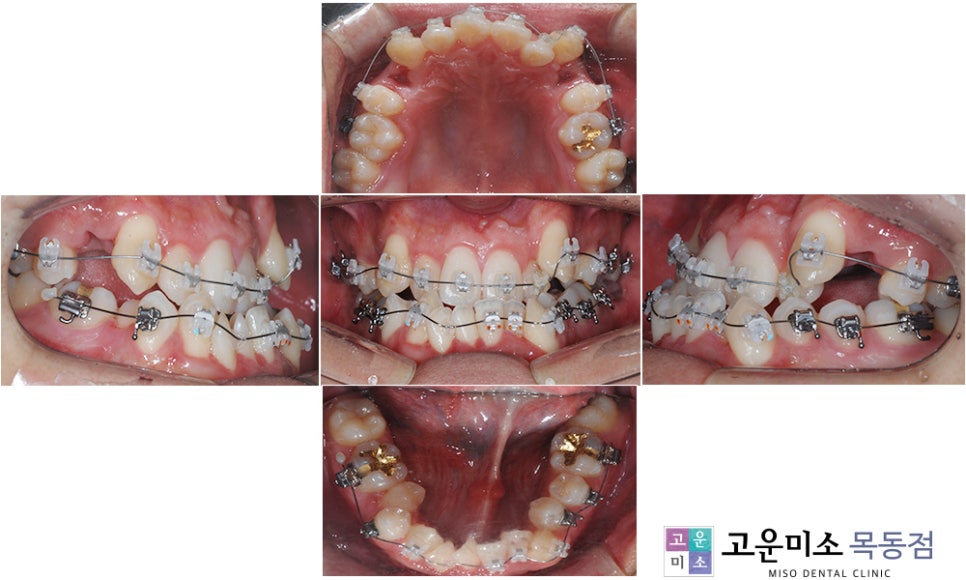

치아교정과 양악수술을 병행하는 경우,

수술 전 교정을 통해 수술에 적합한

치아 배열을 만들어 둡니다.

이후 양악수술을 진행하게 되죠.

수술 전 교정은 수술 시 악골을 적절한 위치로

배치할 수 있도록 돕는 데 초점을 맞추며,

일반적인 교정 방법과는 차이가 있습니다.

이 과정에서는 윗니는 안쪽으로,

아랫니는 바깥쪽으로 향하도록 배열을 조정합니다.

정상적인 교합에서는

윗니가 아랫니를 덮어야 하지만,

반대교합인 경우 이 관계를 회복해야 합니다.

즉, 아래턱이 과도하게 나와 있어

앞니의 관계가 반대로 되어 있는 상태에서

이를 정상으로 되돌려야

수술 후 교정이 원활하게 진행될 수 있습니다.

따라서 수술 전 교정 동안에는

아래턱이 더욱 돌출되어 보이고,

입이 나오면서 발음이 불편하거나

심미적인 불편함이 발생할 수 있습니다.

하지만 이 부분은 수술 후 바로 해결되므로

지나치게 걱정할 필요는 없습니다.